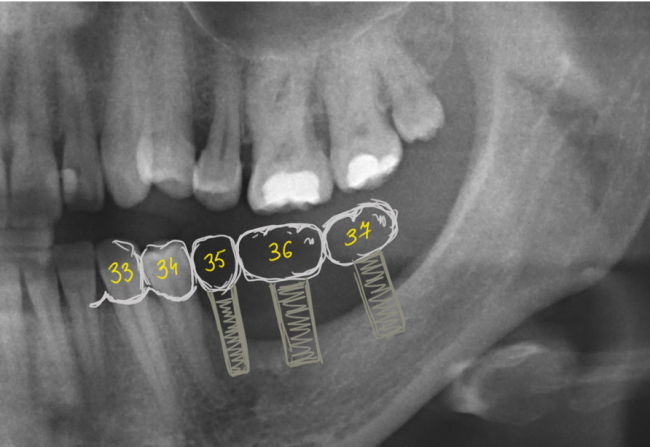

Планируем данную работу

2 или 3 импланта в область отсутствующих 35, 36, 37 зубов, плюс ортодонтическое лечение — интрузия зубов-антагонистов на верхней челюсти.

По данной схеме уже видно, какого объема костной ткани нам не хватает. В дополнение к снимкам, в клинике мы часто делаем диагностические модели, на которых восстанавливаем зубы и отсутствующую костную ткань с помощью воска — это т. н. WaxUp. Так мы моделируем и можем увидеть конечный результат нашей работы и планировать операцию. К сожалению, WaxUp показать не могу (поленился сфотографировать, лошара ;-)).

Это вполне осуществимо с помощью операции остеопластики, «наращивания костной ткани».

- Три или два импланта? При отсутствующих трех зубах мы можем обойтись двумя имплантами. Это будет мостовидный протез с опорой на импланты 35 и 37 зубов. Минусы — мостовидный протез требует более тщательного ухода. Плюсы — он дешевле. При установке трех имплантов мы можем изготовить на каждый имплант одиночную коронку. В этом случае существенно облегчается гигиена и уход за зубами, а сами зубки выглядят более естественно. Минусы — это дороже.